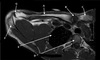

How well did you know this?

1

2

Q

3

What is letter A?

A

CORACOID PROCESS

4

What is letter B?

DELTOID MUSCLE